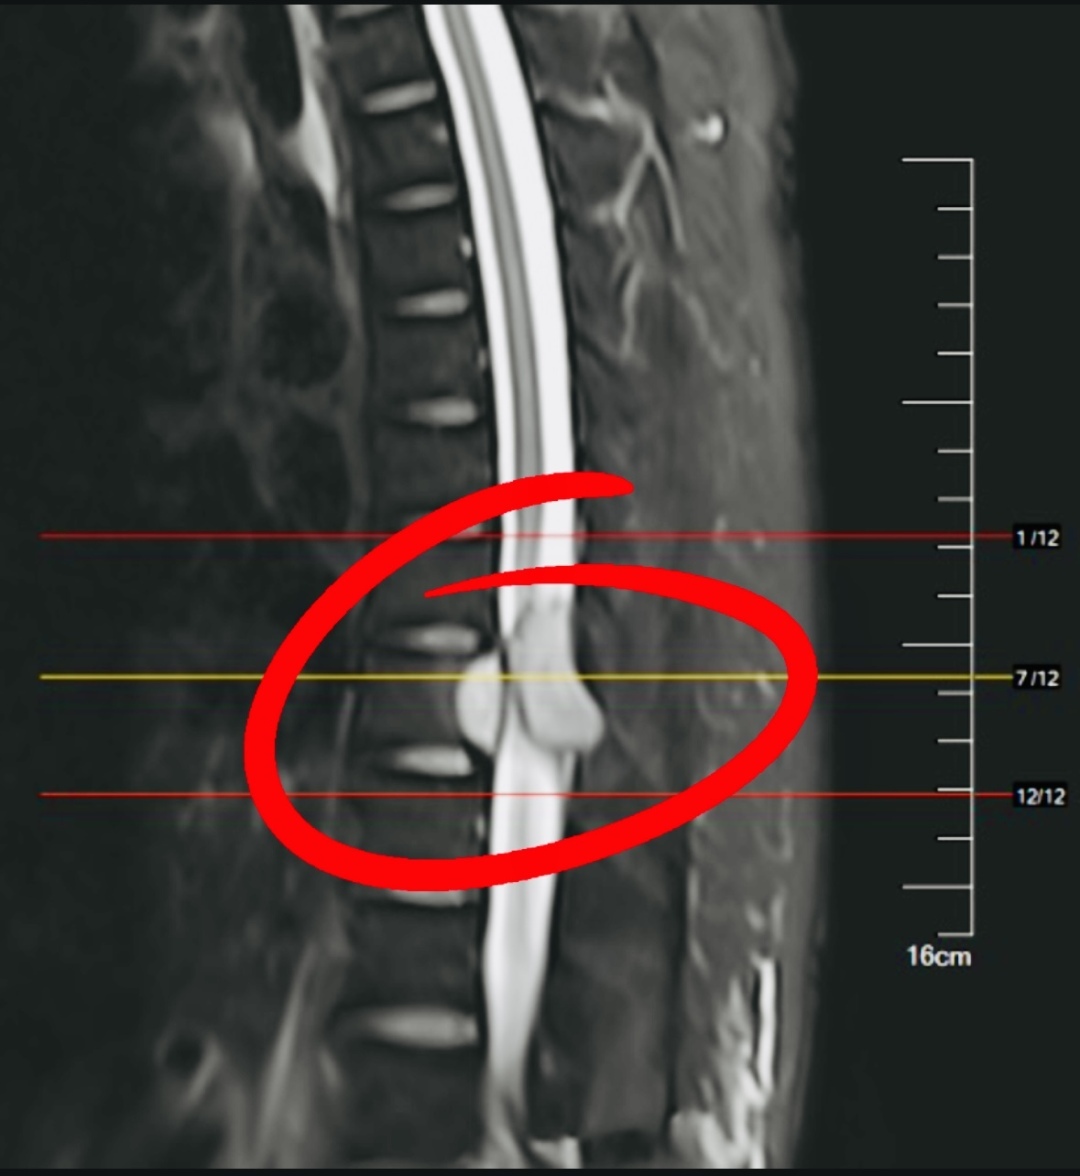

该科主任医师钱东阳和团队在仔细检查后发现,胸椎转移的肿瘤组织已经严重压迫到纪阿姨的脊髓,这是引起她下肢失去知觉瘫痪在床的原因。想要恢复下肢运动感觉,必须接受手术,解除肿瘤压迫,但手术有风险,而且瘫痪已超过48小时,术后下肢运动和感觉能恢复到什么程度不好说。

纪阿姨和家人恳请医生“放手一搏”。于是,经充分评估后讨论,钱东阳医生团队迅速行动,仅两小时后就开始了急诊手术。术中,医生们细致地切除了大部分转移的肿瘤组织,并对受压的脊髓进行充分减压,同时还采用微波消融技术对椎体转移肿瘤充分灭活,并对残留椎体进行骨水泥填充,增强了脊柱的稳定性。

出院后,在医护人员的专业治疗指导和家人的精心照料鼓励下,纪阿姨坚持药物治疗和康复锻炼,不仅站起来了,还一步步迈开腿,半年左右便逐渐能拄着拐杖走路。一年后她再次复查,发现曾经严重受压的脊髓再次恢复了通畅,而且病情控制得很好,肿瘤没有复发。